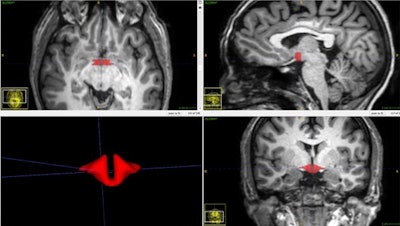

Brain MRI depicts hypothalamus in red.Oral contraceptives are also used to treat a host of conditions, including irregular menstruation, cramps, acne, endometriosis, and polycystic ovary syndrome. A 2018 report from the U.S. Centers for Disease Control and Prevention's National Center for Health Statistics found that from 2015 to 2017 approximately 47 million women ages 15 to 49 in the U.S. reported current use of contraceptives. Of those, 12.6% used the pill, according to the RSNA release.